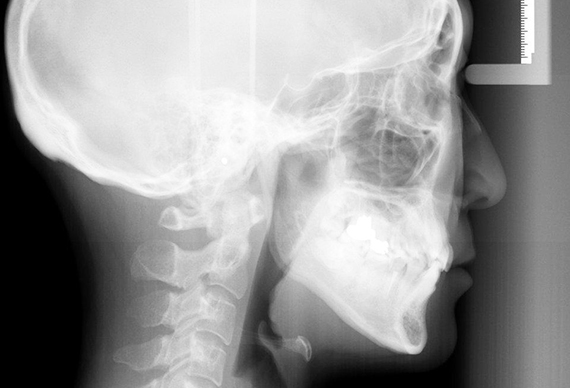

頭部のレントゲン

「セファログラム」とは

当院の矯正治療では、セファログラムを使用して精密な診断と治療を行っています。

セファログラムは、顔面や頭部の断面を撮影するレントゲンで、普通のレントゲンと異なり、顎の形や歯の傾き、口元のバランスを立体的に把握できます。これにより、矯正治療の経過を正確に把握し、患者さま一人ひとりに合った繊細な歯列矯正が可能になります。